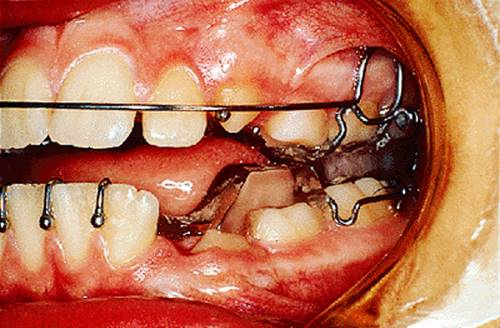

Where the upper molars are clasped, there can be no spontaneous expansion of the upper arch while the activator is being worn. Therefore it is necessary to fit an expansion appliance first, such as that shown in Fig. 18.8. This gives the patient an easy introduction to appliance wear, and it may also include springs to improve the alignment of the upper incisors. In cases where a fixed appliance has been used to align the arches before fitting the functional appliance, the medium opening activator design can be modified to fit around fixed attachments (Fig. 18.2).

Fig. 18.8. Expansion appliance fitted prior to the functional appliance.